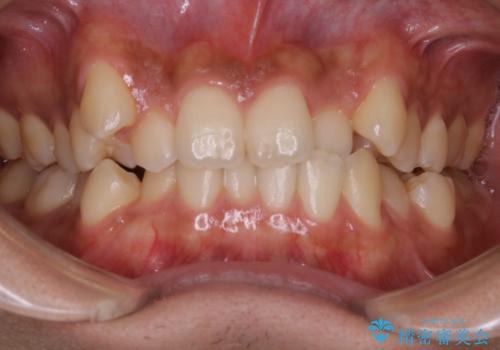

インビザライン単独でここまでできる!!抜歯矯正

- 治療計画

- マウスピースによる矯正治療をご希望された方です。歯のガタつきが大きかったため、ワイヤーによる抜歯矯正をご提案しました。どうしてもマウスピースが良いとの強いご希望があったため、治療の途中でワイヤー治療に切り替える可能性もあることを十分ご理解いただいた上でインビザラインによる抜歯矯正治療を行いました。

1日20時間以上、正しくインビザラインを使用して頂いたおかげで、ワイヤーに切り替えることなく矯正治療を終了することが出来ました。周囲からも歯並びがすごく綺麗になったと言われたのことで大変ご満足いただけました。